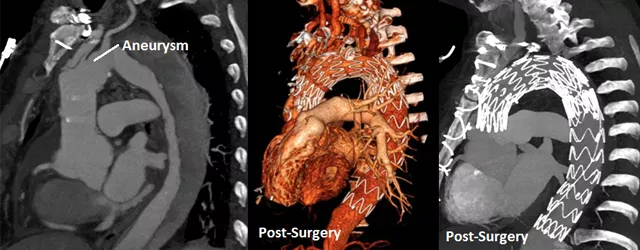

Patient scans of aortic aneurysms

Andy Alvarez, 67, lost his voice—and almost his life—following surgery for a thoracic aortic dissection/aneurysm. An aneurysm is a “ballooning” in the chest cavity of a weakened aorta, the artery that carries blood from the heart to the rest of the body. Today, as Alvarez is celebrating his latest test results, he is speaking out to advise others about how to beat this “silent killer.”

Compounding the second surgery, Tufts MC’s medical team determined that Alvarez also needed thoracic endovascular aortic repair (TEVR), a minimally invasive procedure in which a catheter is used to insert a thin tube called a stent graft that reinforces the aneurysm and helps prevent it from bursting. A month of hospitalization was followed by two weeks of rehabilitation, and Alvarez returned home, hopeful that he would recover without further intervention but mindful that he needed to maintain a healthy lifestyle and check for aneurysm growth.

Finally, in November 2017, Alvarez required a second TEVR by Dr. Salehi to treat an abdominal aortic dissection. Unlike open surgery, this procedure results in less bleeding and faster recovery.